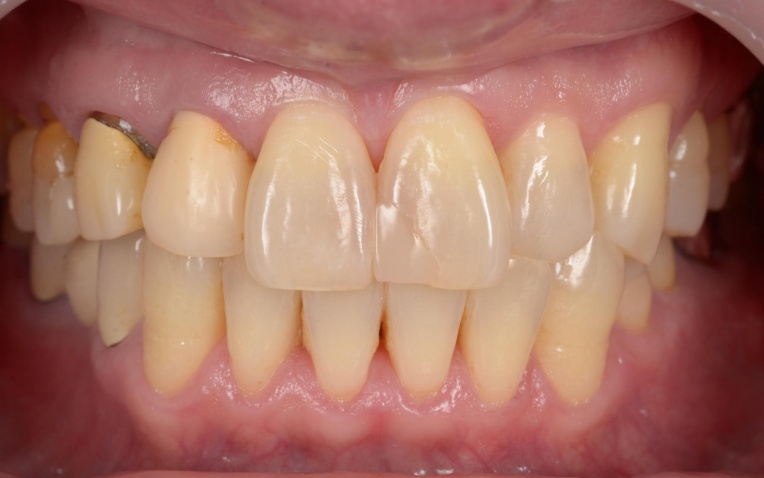

治療前

治療中

まず、ワイヤー矯正装置を用いた矯正治療を開始します。

折れている歯を一時的に利用しながら、受け口傾向にある噛み合わせが改善するよう、歯の位置を少しずつ調整していきました。

歯や歯茎の状態、噛み合わせの変化を確認しながら、目標とする歯並びと噛み合わせに近づくよう治療を進めました。